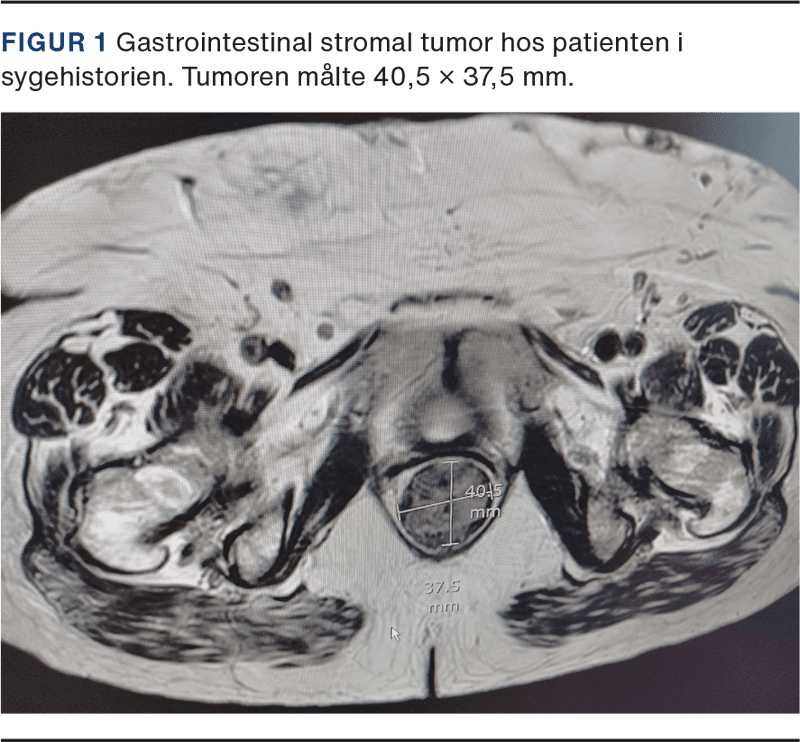

Hun blev diagnosticeret med en GIST på 7 cm i diameter i rectum og fik foretaget biopsi ved transrektal UL-skanning. Biopsien var uden mitoser, og mutationsanalysen viste en deletion i receptor KIT exon 11. Patienten fik imatinib 400 mg × 1 dgl. for at reducere tumorstørrelsen, men fik svære hudbivirkninger, og behandlingen blev skiftet til nilotinib, en andengeneration-TKI. Efter ni måneders behandling var der opnået 40% tumorreduktion. Tumoren målte nu 4 cm i diameter og muligheden for kurativ kirurgi blev revurderet. Patienten var fortsat alment svækket, klassificeret som ASA 3, og hun blev derfor ikke vurderet til at være egnet til kirurgi, hvorfor behandlingen med nilotinib fortsatte. Et år senere var der bedring i patientens almentilstand, mens tumorstørrelsen fortsat var 4 cm i diameter (Figur 1). Efter i alt 20 måneders behandling med TKI fik patienten foretaget transvaginal resektion af GIST. Der blev lavet en miniepisiotomi på begge sider af vagina og en Lone Star APS retractor blev placeret. Herefter blev vaginalvæggen incideret, og tumoren blev fridissikeret med LigaSure og fjernet uden brud af kapslen, inkl. adhærent rectumslimhinde. Herefter lukkedes defekten i rectum, septum rektovaginale samt vaginaslimhinden lagvist med resorberbare suturer.